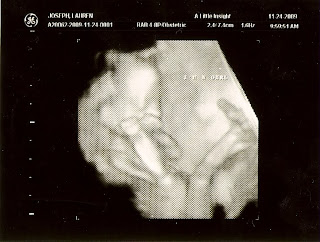

Here are pictures from our 11/24/09 ultrasound- she is 17 weeks 2 days and growing strong!

She loves her hands at her mouth! There were a few times she had her hand in her mouth but we didn't get apicture of that.